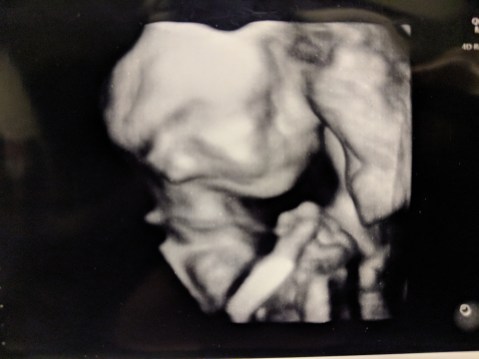

In April 2018, my wife and I discovered we were expecting our first born. In August, our unborn son was diagnosed with Gastroschisis–there was a hole in his stomach and his intestines were on the outside of his body. I documented the experience as from diagnosis to discharge from the NICU.

- The Birth Story. I wrote this in the 48 hours after my son’s birth so as not to forget a thing.